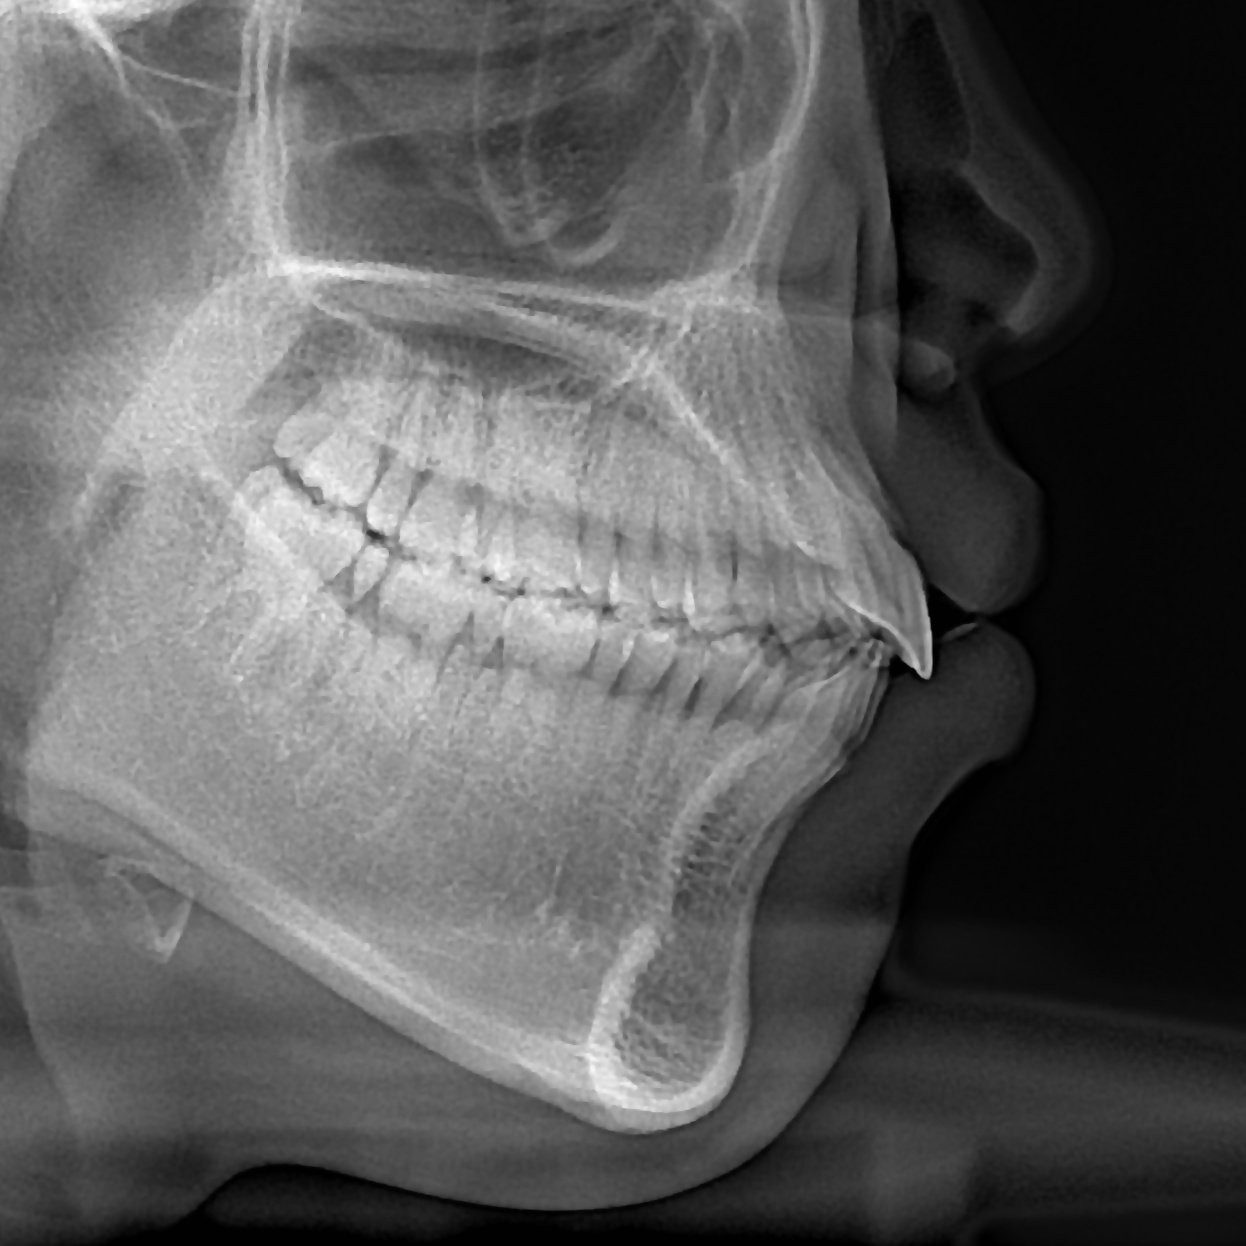

돌출입의 경우 입술의 두께, 앞니의 각도, 후방이동시켜야 하는 양 등을 종합적으로 고려하여 발치 유무를 결정합니다.

위 케이스에서는 발치교정을 이용하여 치아를 후방이동시켜 돌출입을 해소하였습니다.

총 교정기간은 18개월입니다.